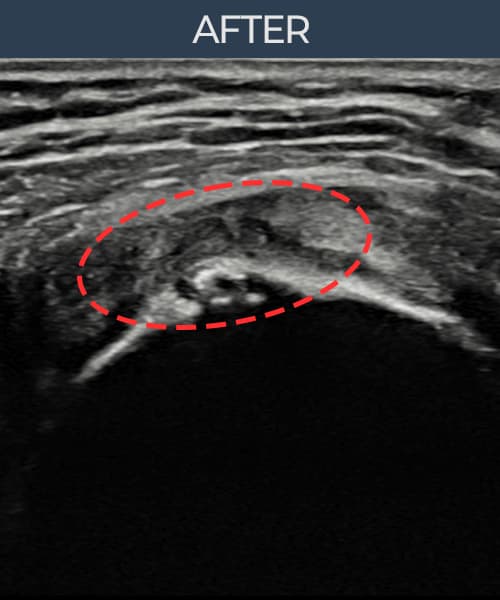

실제 환자의 시술 전후 초음파 영상입니다.

수술 없이 이뤄낸 회복을 직접 확인하세요.

모든 초음파 영상은 실제 환자의 동의를 받아 게시하였습니다. 개인차가 있으며 동일한 결과를 보장하지 않습니다.